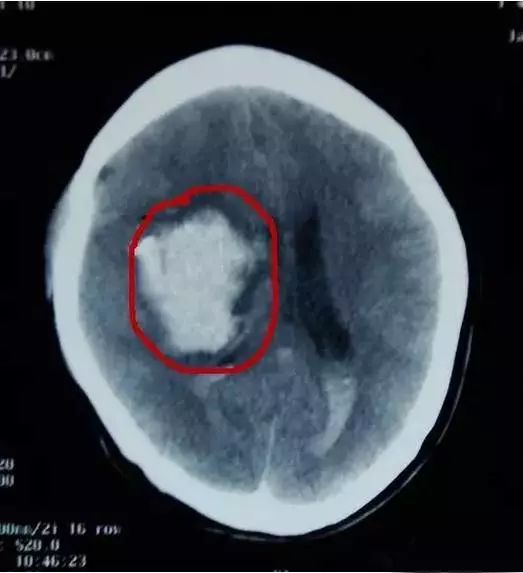

经医生诊断后得知:两个婴儿均为颅内出血且因失血过多出现贫血症状,

最后紧急做了开颅手术,才保住两个宝宝的性命!

迟发性外伤性颅内出血,以3岁以下的幼儿居多,6小时内的发生率较高。迟发性外伤性颅内出血并不在事发当时就表现出异样,因而往往导致就诊不及时,造成严重后果。

宝妈们就要怀疑,是否是迟发性外伤性颅内出血。出现这些症状,一定要及时到正规医院做相关检查,如头颅CT等。宝宝脑外伤24小时内视察很重要,尤其是外观不明显的脑外伤。